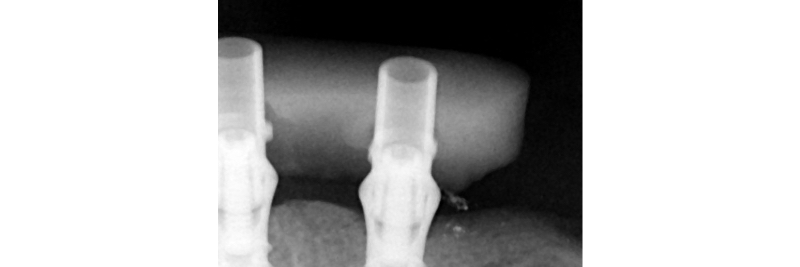

Jig fastened to the implants. One screw test is performed to confirm passivity.

Radiographic verification of the temporary cylinder fully seated on the implant platform.